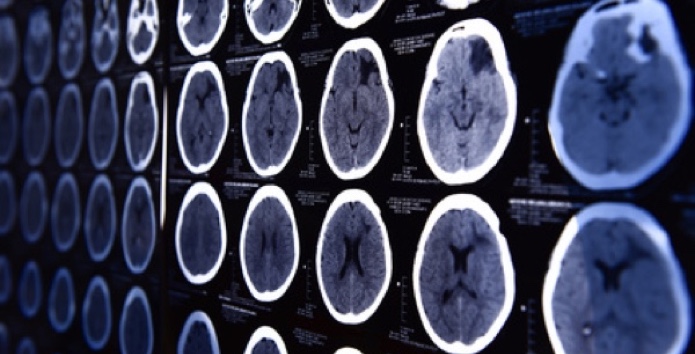

Im Diakonie Klinikum Siegen, Raum Köln-Bonn, profitieren Patienten mit Hirntumor von neuester Technik RAUM KÖLN/BONN. Die Diagnose Hirntumor ist für Patienten und Angehörige eine Situation größter Belastung. Umso wichtiger ist es für Betroffene zu wissen, dass sie die für sie bestmögliche Behandlung erhalten können. Die Neurochirurgie im Klinikum Jung-Stilling in Siegen hat jetzt mit einer…